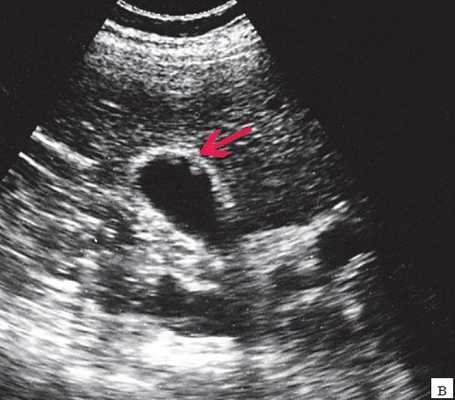

(Слева) На КТ без контрастного усиления у пожилого мужчины с ишемической болезнью сердца и сахарным диабетом, предъявляющего жалобы на боль в животе, визуализируются включения газа в стенке и просвете желчного пузыря. Обратите внимание на свободный газ в брюшной полости - признак перфорации желчного пузыря. При патоморфологическом исследовании подтвердился трансмуральный некроз желчного пузыря, были выявлены также грам-отрицательные палочковидные бактерии.

(Справа) На продольной сонограмме желчного пузыря у пожилого мужчины, страдающего сахарным диабетом, определяется отек стенки желчного пузыря с наличием интрамуральных включений газа - характерные изменения для эмфизематозного холецистита.

4. КТ признаки эмфизематозного холецистита:

• Лучший метод идентификации газа в просвете желчного пузыря и в его стенке, характеризующийся стопроцентной чувствительностью:

о Может также обнаруживаться газ в перихолецистическом абсцессе или свободный газ в брюшной полости (при перфорации)

о Редко - при ишемии стенки желчного пузыря - появляется газ в воротной вене

о Распространение газа в другие отделы билиарной системы подозрительно на тяжелую форму инфекции

• Желчные камни обнаруживаются приблизительно у 50% пациентов: акалькулезный холецистит связан с более высоким риском